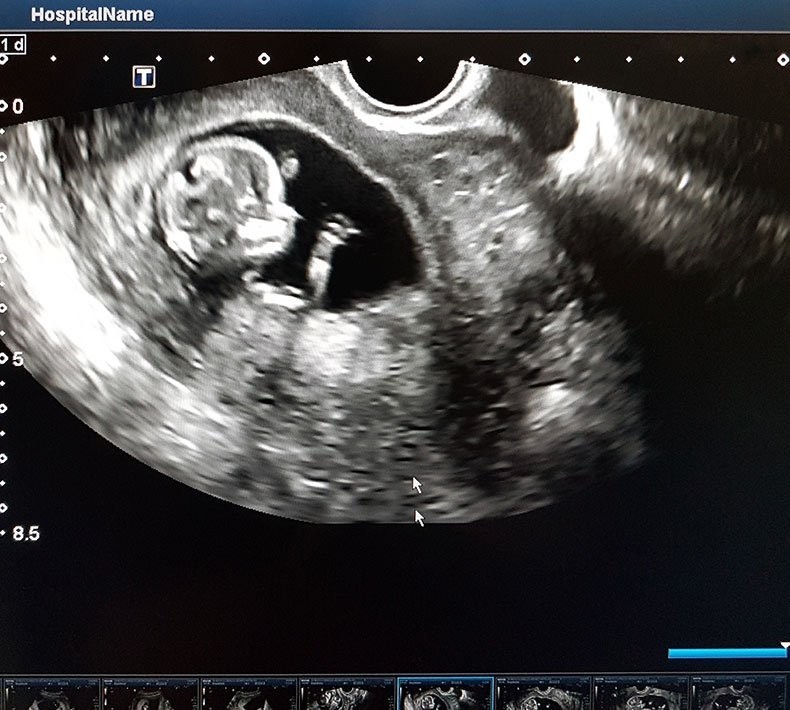

ภาพจาก th.theasianparent.com

ตรวจหาหรือยืนยันอายุครรภ์ สตรี จำนวนไม่น้อย ที่ไม่ทราบวัน ที่มีประจำเดือนครั้งสุดท้าย หรือมีประจำเดือนไม่แน่นอน จะทำให้คะเนวันกำหนดคลอดได้ยาก การตรวจด้วยอัลตราซาวนด์ เพื่อวัดส่วนต่าง ๆ ของทารก เช่น ความยาวของตัวทารก (Crown Rump Length) การวัดขนาดศีรษะของทารก การวัดขนาดความยาวต้นขา และวัดเส้นรอบบวง ช่องท้องของทารก จะช่วยทำให้นำมาคาดคะเนอายุครรภ์ของทารกในครรภ์ได้